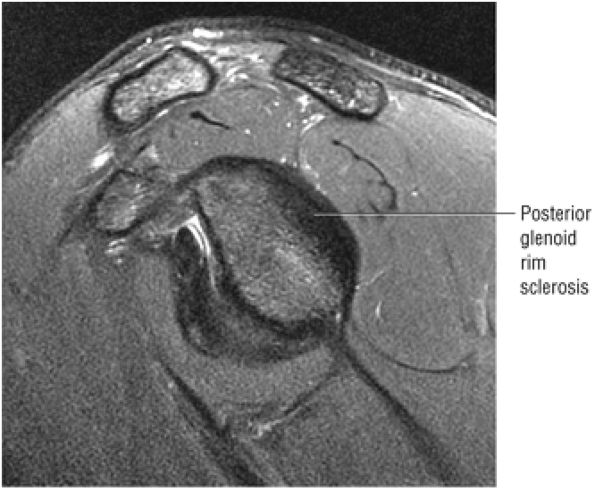

The glenoid fossa is evaluated in the sagittal plane for patterns of glenoid rim and fossa sclerosis associated with instability and osteoarthritis.